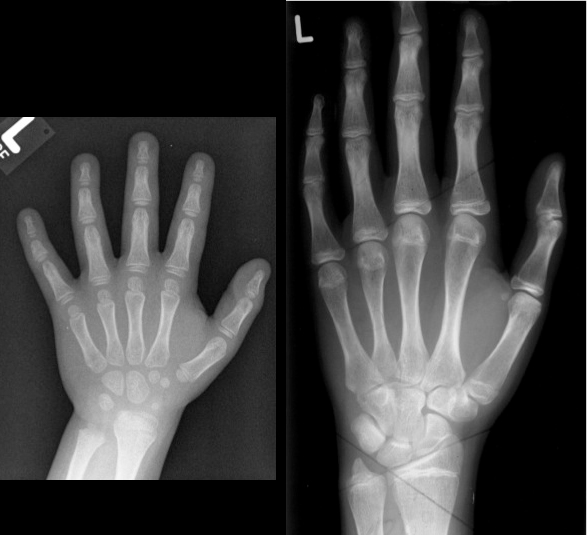

Größenvergleich der Hand vom Kleinkind und Jugendlichen